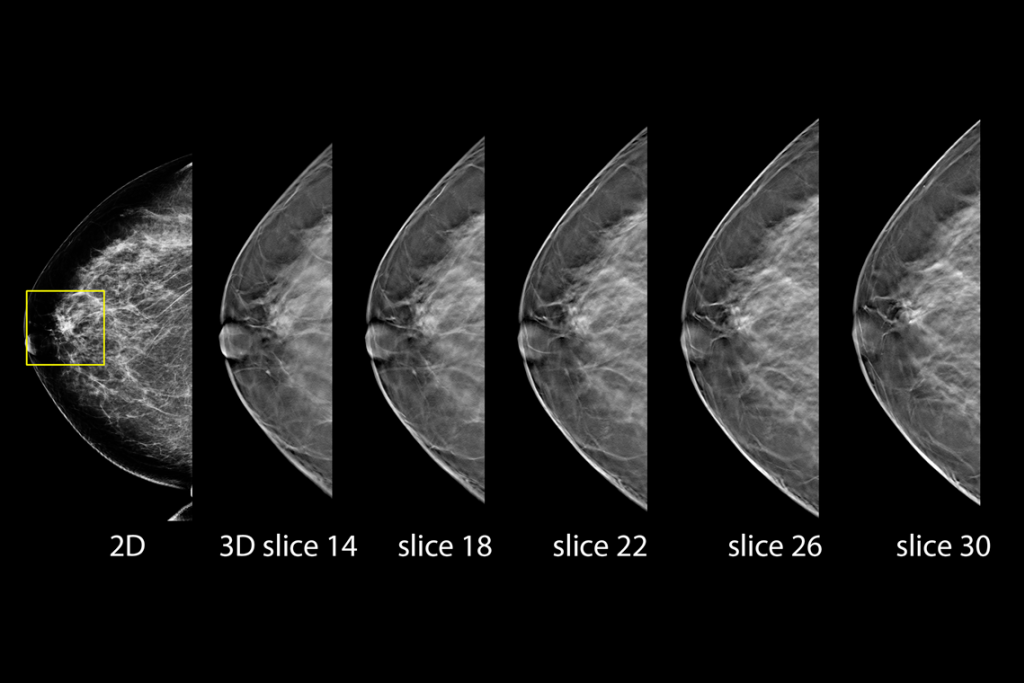

Clinical Images

Clinical images of breast scan mammography

Clinical images of breast scan with suspicious Lesion

Clinical images of breast scan